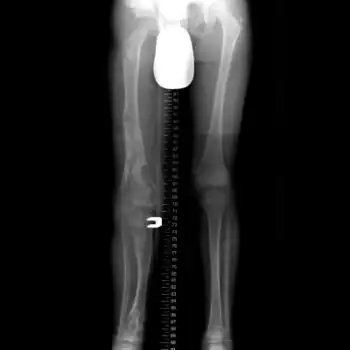

X-ray hips and legs: multiple enchondroma

X-ray legs: Ollier disease